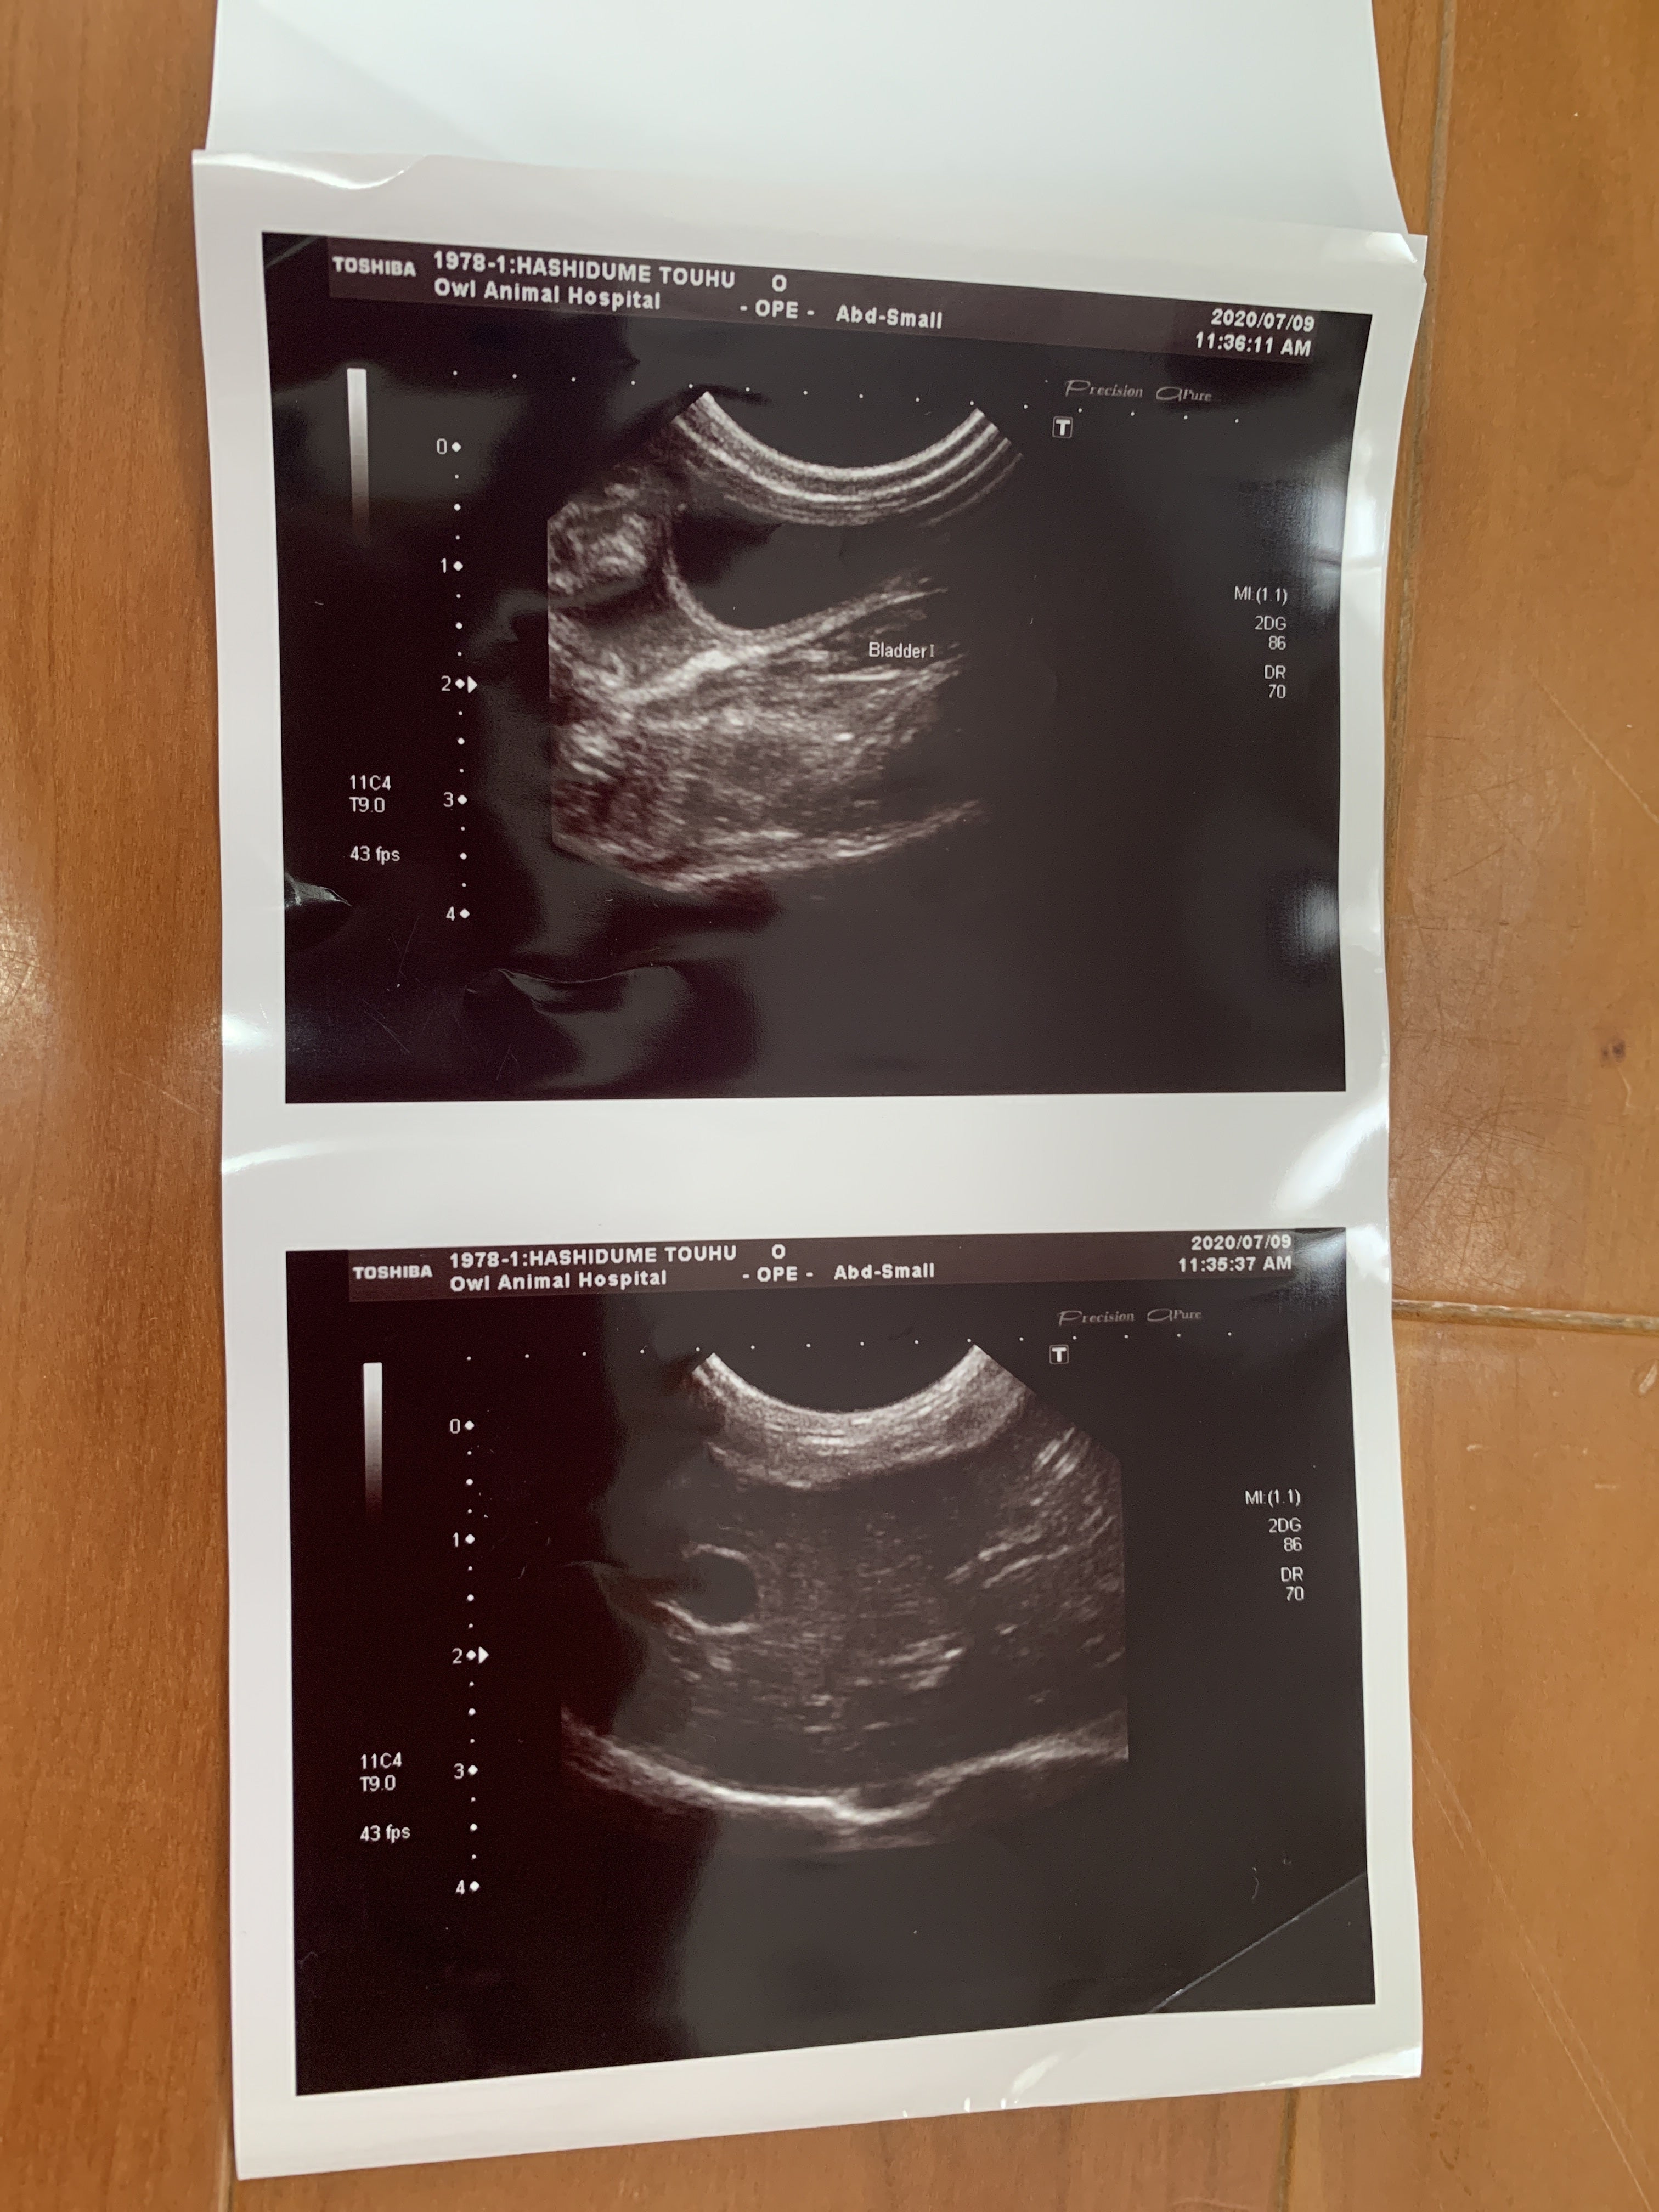

7月9日 朝から病院に連れて行きました。血液検査とエコーの結果

ここで初めて猫伝染性腹膜炎かも知れないと言われました。少しお腹が膨らんでいるのは便秘ではなく腹水でした。私は初めてその病名を聞きました。先生が言うには、このFIP と言う病気は進行が早く数日〜2か月で亡くなる怖い怖い病気ですとの事でした。その後の先生の話を涙が流れるのを必死にこらえて聞いていました。

ウェットタイプは腹水が溜まっていくので、見た目も分かるし、腹水を使った検査でFIP と分かるので診断が早い。